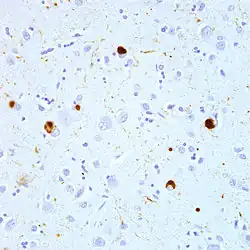

| Micrograph of a section of the cerebral cortex from a person with Alzheimer's disease, immunostained with an antibody to amyloid beta (brown), a protein fragment that accumulates in amyloid plaques and cerebral amyloid angiopathy. 10X microscope objective. |